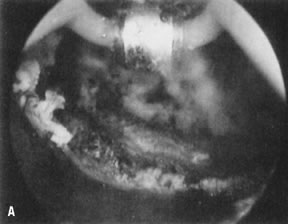

Although alternative methods for the surgical transection of adhesions can be used, such as the resectoscope and/or fiber lasers with a low energy output, the mechanical approach using hysteroscopic scissors seems more logical, particularly to avoid peripheral damage to the remaining healthy endometrium, which will be the reservoir for rapid uterine cavity reepithelialization after treatment (Figs. 31, 32, 33, 34, and 35; see Color Plate 1G, ).39,40

Fig. 31. Lateral intrauterine adhesion at right uterine cornual region. Scissors approaching adhesion for division.

Fig. 32. Hysteroscopic division of adhesion.

Fig. 33. Uterine cavity symmetry reestablished after hysteroscopic treatment.

Fig. 34. A. Thick fundal adhesion close to uterotubal cone. B. Hysteroscopic division with scissors.

Fig. 35. Hysterosalpingogram shows complete uterine cavity occlusion by adhesions.